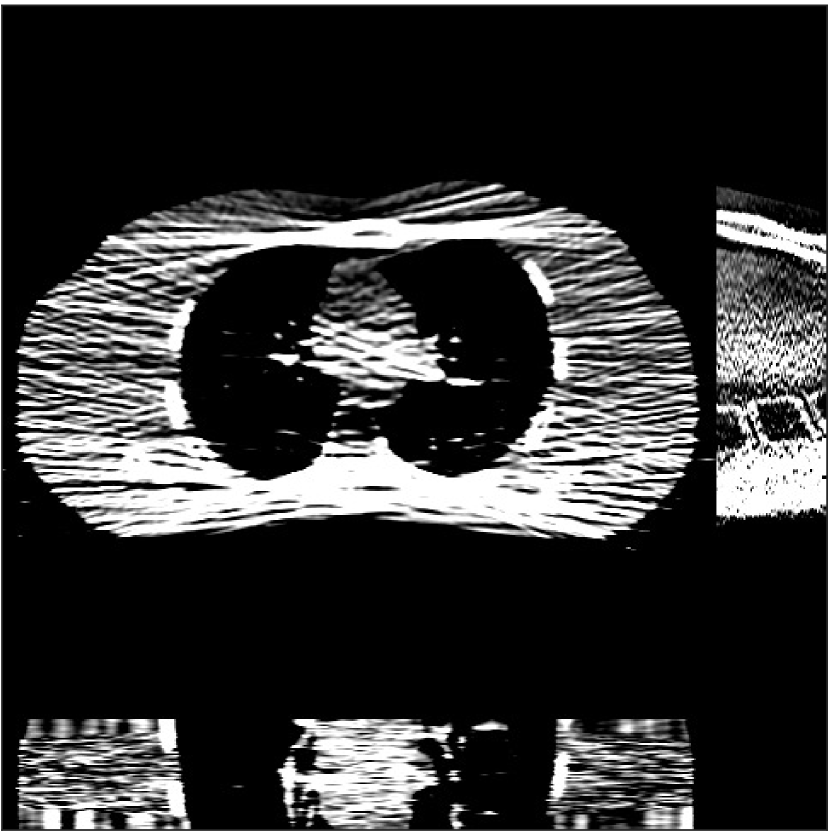

Fig. 4 shows the reconstructed images and the corresponding error images for PWLS-EP, PWLS-ULTRA, and SPULTRA, at and . Compared to the PWLS-EP result, both PWLS-ULTRA and SPULTRA achieved significant improvements in image quality in terms of sharper reconstructions of anatomical structures such as bones and soft tissues, and suppressing the noise. However, the PWLS-ULTRA method introduces bias in the reconstructions, which leads to larger reconstruction errors compared to the proposed SPULTRA method. In Fig. 4, we marked three 3D ROIs in the axial plane, i.e., ROI 1, ROI 2, and ROI 3. Fig. 5 shows the zoom-in images of a 3D plot of ROI 1, and those of ROI 2 and ROI 3 are shown in the supplement. We also plot the evolution of RMSE through the axial slices of the three 3D ROIs in Fig. 6. The figures demonstrate that SPULTRA clearly outperforms the competing PWLS-EP and PWLS-ULTRA schemes.

The above advantages of SPULTRA can be seen more clearly when observing the image profiles. Fig. 7 plots the image profiles for the three methods together with that of the ground-truth image. Fig. 4 shows the horizontal green solid line and the vertical red dashed line, whose intensities are plotted in Fig. 7. It is obvious that the profiles for SPULTRA are closest to the ground-truth among the three compared methods. The gap between the profiles of the PWLS-based methods and the ground-truth shows the bias caused by the compared PWLS methods.

Fig. 9 shows three axial slices from the 3D reconstructions with SPULTRA and PWLS-ULTRA at : the middle slice (No. 67) and two slices located farther away from the center (No. 90 and No. 120). The image profiles along a horizontal line (shown in green) in the displayed slices are also shown in Fig. 9. The reconstructed slices using PWLS-ULTRA appear darker around the center compared to the “true” clinical image and the reconstructions with SPULTRA. This means PWLS-ULTRA produces a strong bias in the reconstruction. The bias can be observed more clearly in the profile plots: the pixel intensities for the SPULTRA reconstruction better follow those of the “true” clinical image, while those for the PWLS-ULTRA reconstruction are much worse than the “true” values. Moreover, SPULTRA achieves sharper rising and failing edges compared to PWLS-ULTRA. In other words, SPULTRA also achieves better resolution than PWLS-ULTRA. Fig. 9 also shows a zoomed-in ROI for each of the chosen slices, and highlights some small details with arrows. It is clear that in addition to reducing the bias, SPULTRA reconstructs image details better than PWLS-ULTRA.